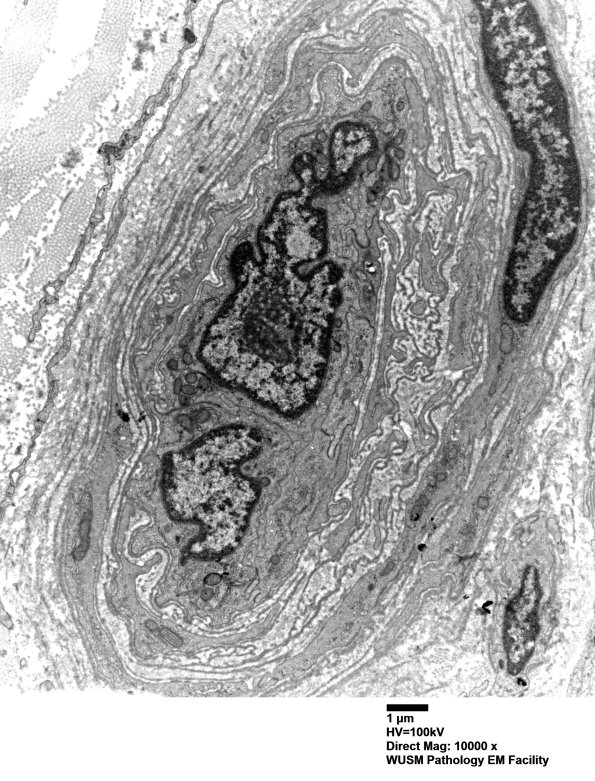

Washington University Experience | PERIPHERAL NEUROPATHY | 11 VASCULITIS - VASCULOPATHY | 2 Vasculopathy | 16B7 (Case 16) HIEM EM026 - Copy

16B7,8 There are numerous fragments of basal membranes (arrows, 16B8) within the abnormal vessel wall. (electron micrographs)